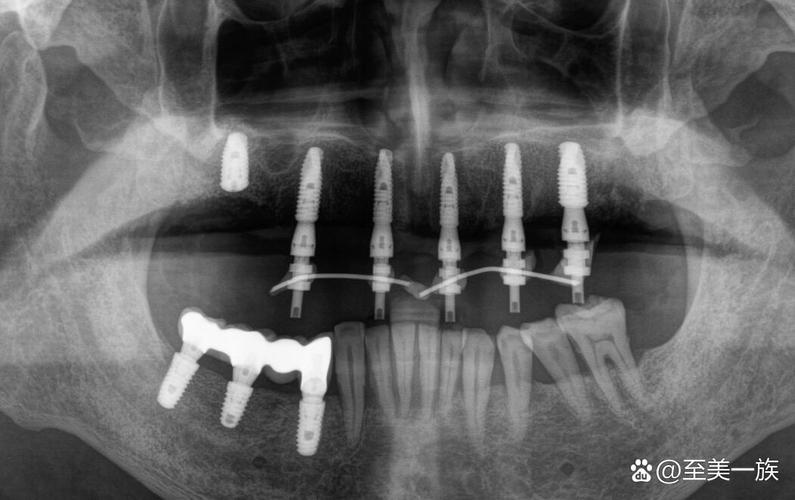

- 伪影: 虽然钛种植体本身不会产生大量伪影,但它仍然会在MRI图像上产生一定程度的伪影(图像变形或信号缺失),尤其是在种植体周围,伪影的大小和范围取决于种植体的尺寸、形状、位置以及MRI的场强和序列,这可能会影响对种植体周围骨组织或邻近结构的清晰观察,但通常不会导致检查无法进行。

- 产生显著伪影: 会导致严重的图像变形和信号丢失,可能完全掩盖种植体周围及邻近重要结构(如神经、血管、其他牙齿),严重影响诊断准确性。